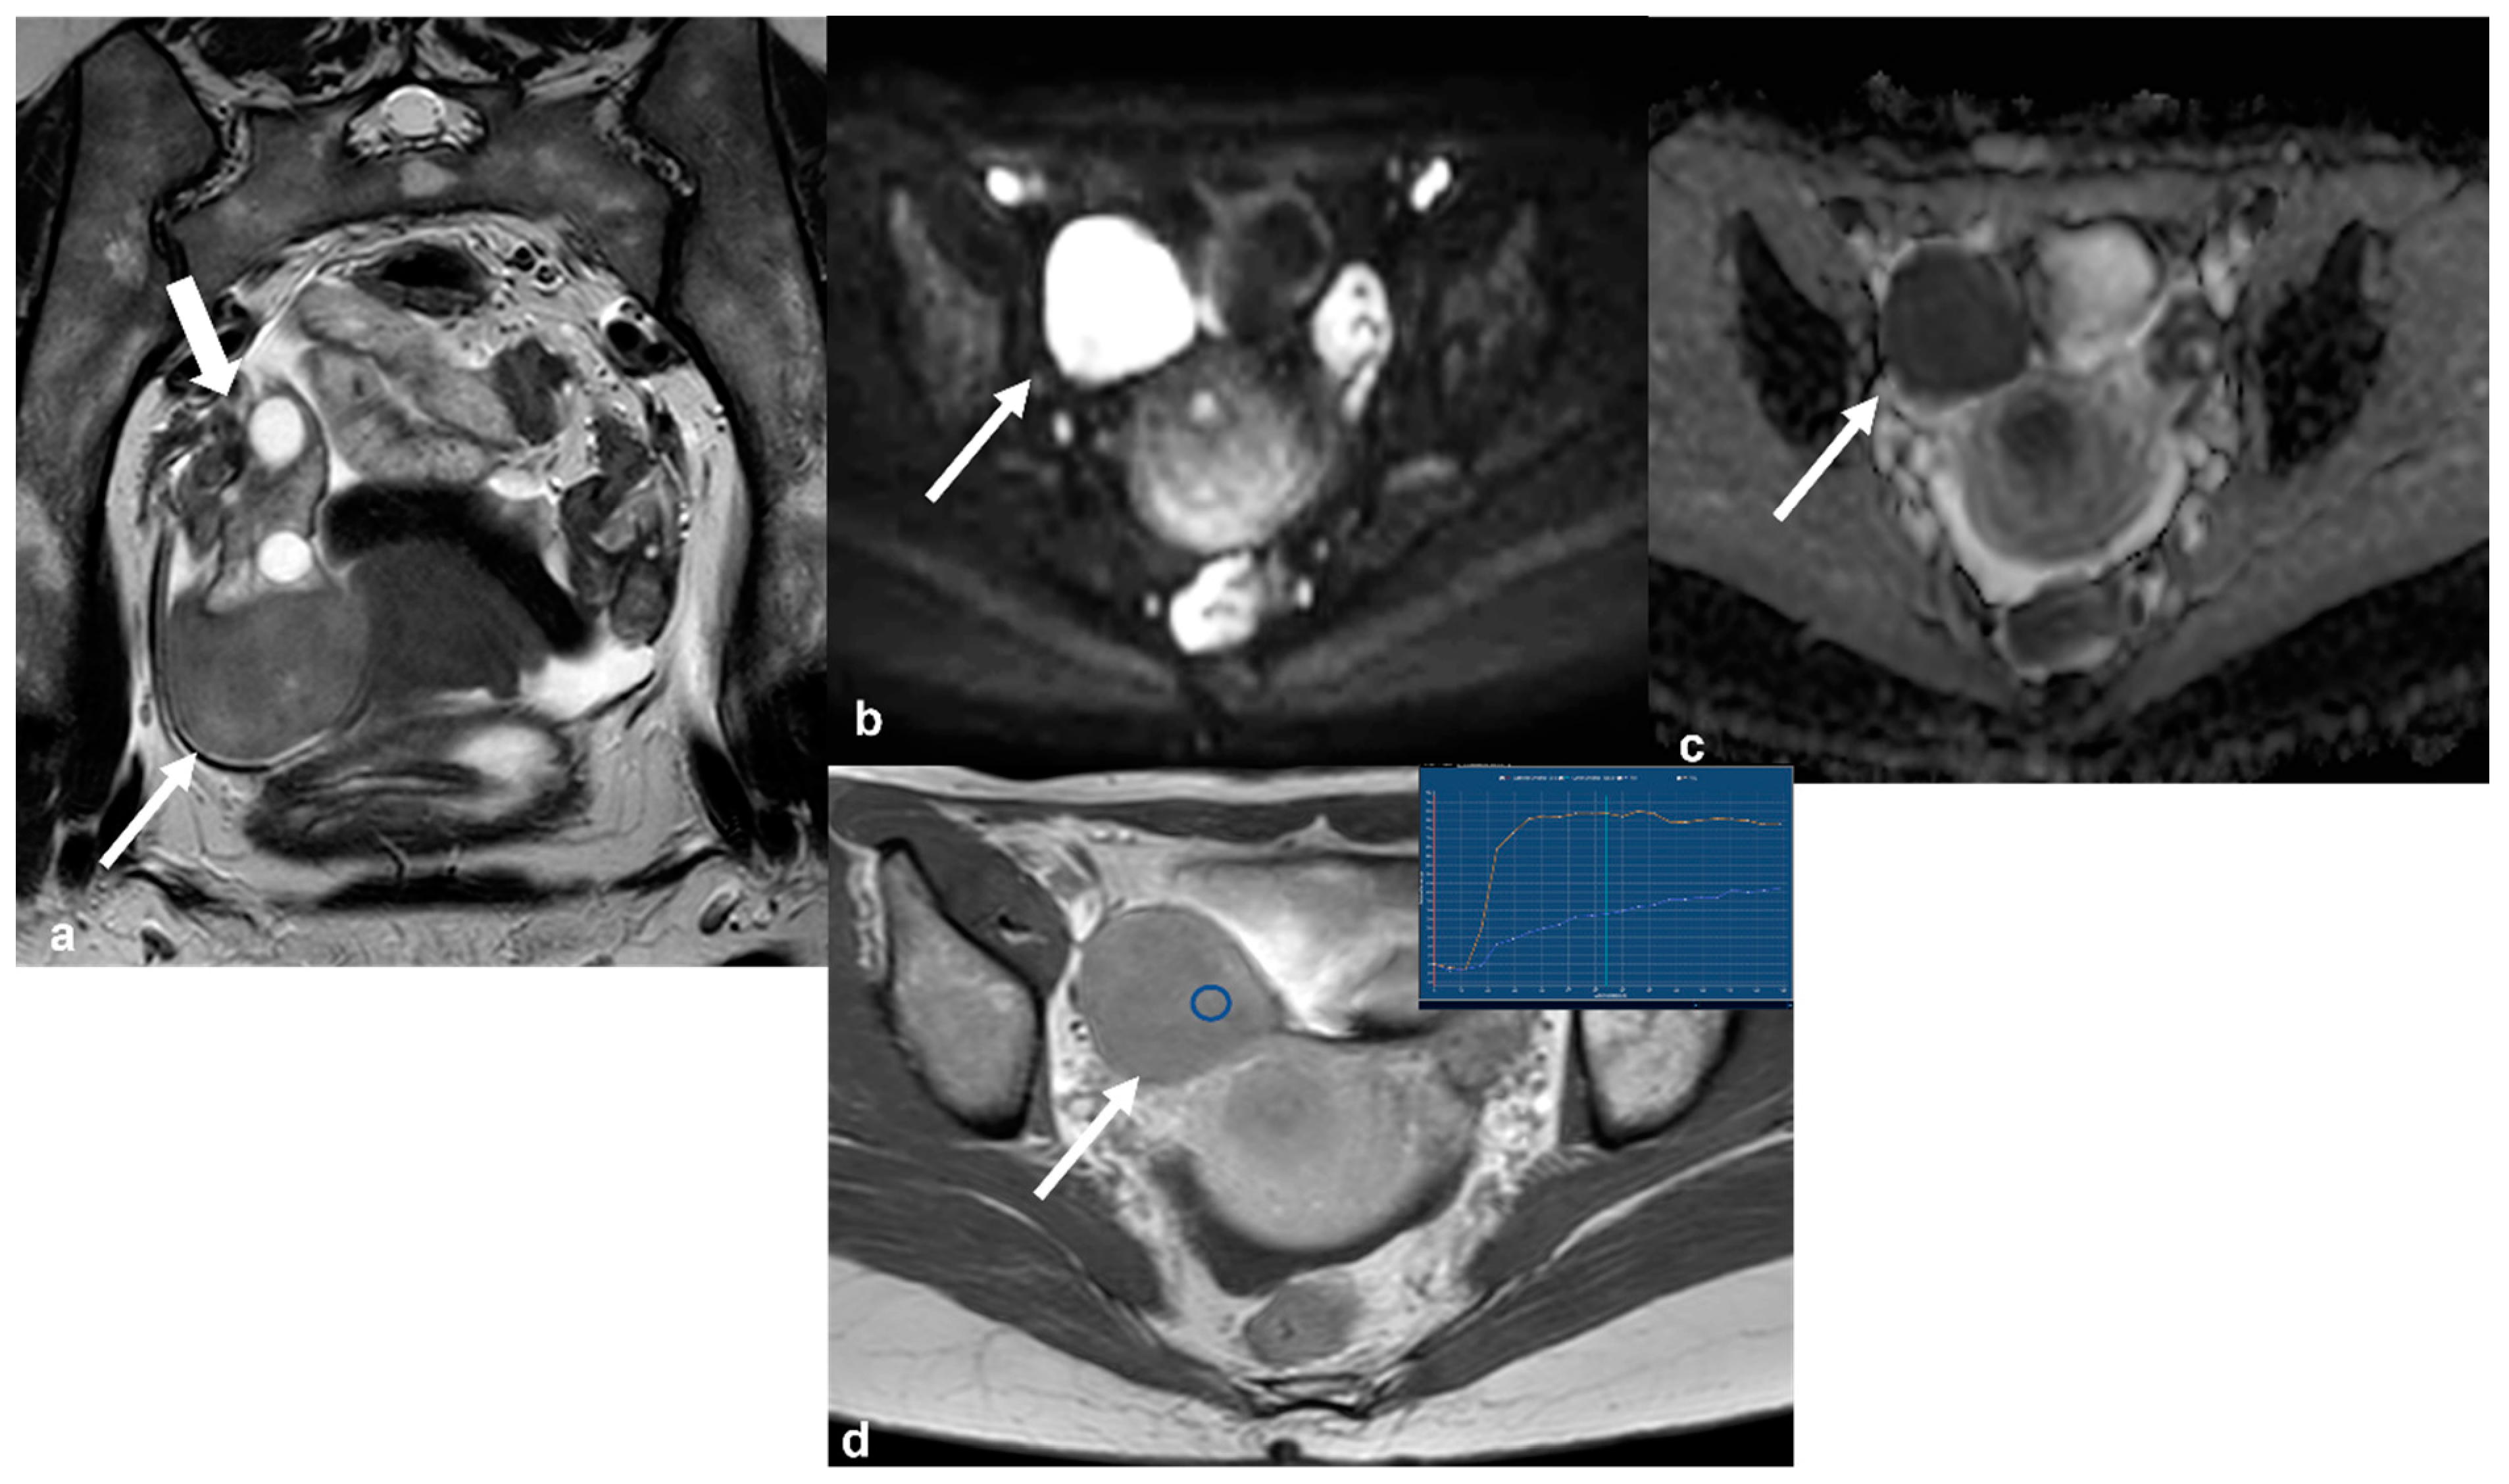

2.5.3. Epithelial Ovarian Cancer

2.6. Non-Ovarian Masses